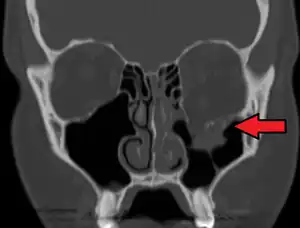

Radiography, imaging of tissues using X-rays, is used to rule out facial fractures.[2] Angiography (X-rays taken of the inside of blood vessels) can be used to locate the source of bleeding.[11] However the complex bones and tissues of the face can make it difficult to interpret plain radiographs; CT scanning is better for detecting fractures and examining soft tissues, and is often needed to determine whether surgery is necessary, but it is more expensive and difficult to obtain.[4] CT scanning is usually considered to be more definitive and better at detecting facial injuries than X-ray.[3] CT scanning is especially likely to be used in people with multiple injuries who need CT scans to assess for other injuries anyway.[12]